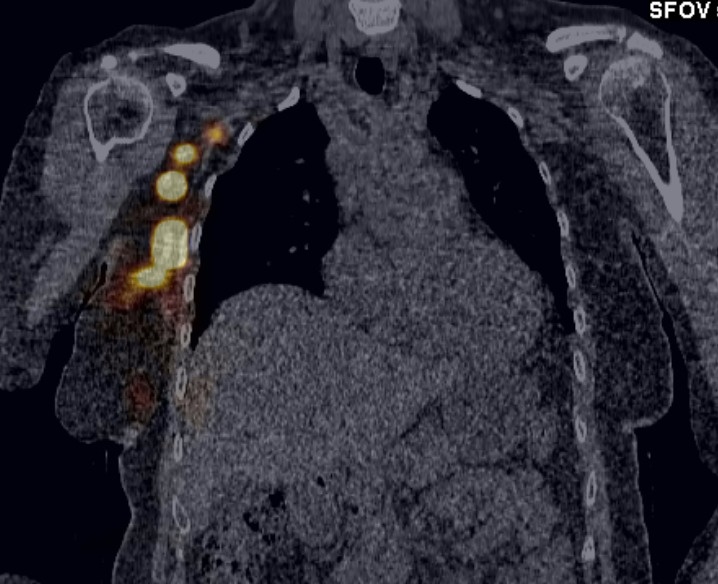

3. Визуализация (ОЀЭКВ/КВ). πŸ“·

ΠŸΠ΅Ρ€Π΅Π΄ ΠΎΠΏΠ΅Ρ€Π°Ρ†ΠΈΠ΅ΠΉ проводят ОЀЭКВ/КВ β€” это исслСдованиС ΠΏΠΎΠΊΠ°Π·Ρ‹Π²Π°Π΅Ρ‚ Ρ…ΠΈΡ€ΡƒΡ€Π³Ρƒ Ρ‚ΠΎΡ‡Π½ΠΎΠ΅ располоТСниС «горячих» Ρ‚ΠΎΡ‡Π΅ΠΊ Π½Π° 3D-ΠΌΠΎΠ΄Π΅Π»ΠΈ Ρ‚Π΅Π»Π°. Π’Ρ€Π°Ρ‡ ΡƒΠΆΠ΅ Π·Π½Π°Π΅Ρ‚, Π³Π΄Π΅ ΠΈΡΠΊΠ°Ρ‚ΡŒ.